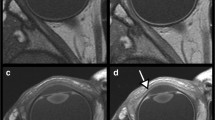

Figure 5 shows representative images (presented only for the samples treated with Gd and 17O). After Gd administration, the TE500 image showed a visual signal decrease in the anterior chamber at 4 h and a strong signal decrease in the vitreous cavity at 26 h; the TE3200 image showed a visual signal decrease in the anterior chamber at 1 h and a decrease in the vitreous peripheral signal at 8 h. After 17O administration, the signal decrease in the anterior chamber was observed on the graph for TE500 (Fig. 3a), but it was visually obscure, and there might be a slight signal decrease visually in the vitreous cavity after 12 h. The TE3200 image showed a visual signal decrease in the anterior chamber at 0.5 h, and a gradual signal decrease in the vitreous cavity from the periphery at 1 h. In both solutions with TE4500, the tendency for signal decrease was more remarkable compared to TE3200. In 3D-real IR images, only the Gd sample showed a strong signal increase. Signal increases in the anterior chamber were observed at 0.5 h, and their distribution in the vitreous cavity gradually increased at 2 h and later.

We also established that there are differences between Gd and 17O with respect to the speed and pattern with which these drugs penetrate the vitreous cavity. Compared with Gd, we found that 17O administered via eye drops was characterized be a more rapid distribution, which is consistent with the findings of a previous study on glymphatic water transport in the rat brain in vivo [16]. In addition, the penetration of Gd into the vitreous cavity may be initiated from the peripheral through the sclera, whereas in contrast, 17O appears to be distributed from the anterior chamber side into the vitreous cavity (Fig. 5). We suspect that these differences in distribution speeds and patterns are attributable to certain pharmacodynamic properties of the drugs, such as differences in molecular weight and viscosity, which is a topic warranting further investigation.